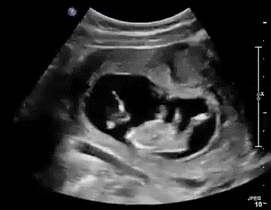

之后的过程也很顺利,四维彩超没有异常,定期产检胎心 NT 正常。到现在 30 多周,眼看“曙光在前”。为了稳妥起见,常杰主任嘱咐张女士继续服药,直到生完孩子,出了月子后再复诊。